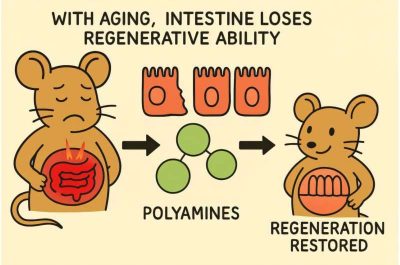

Intestino-immagine: l’invecchiamento riduce la rigenerazione dell’intestino tenue attraverso difetti della proteostasi e accumulo di proteine. Aumentare i livelli di poliammine prima del danno migliora la proteostasi e stimola la proliferazione cellulare, favorendo la riparazione intestinale. Crediti: Leibniz Institute on Aging – Fritz Lipmann Institute

I ricercatori hanno scoperto che durante la rigenerazione dell’intestino tenue dei topi anziani, l’equilibrio dell’omeostasi proteica (proteostasi), ovvero il delicato equilibrio tra sintesi, ripiegamento e degradazione delle proteine, viene alterato.

Di conseguenza, le vecchie cellule intestinali accumulano proteine difettose, o “difettose”, nel tentativo di riparare i danni tissutali. Questo accumulo innesca stress cellulare, che a sua volta ostacola la capacità delle cellule di rigenerarsi efficacemente.

Un confronto della capacità rigenerativa nei topi giovani e anziani ha mostrato che, dopo il danno, i tipici segni di stress proteostatico e livelli elevati di poliammine sono stati osservati solo nell’intestino invecchiato. Le poliammine, come la spermidina e la putrescina, sono piccole molecole cariche positivamente coinvolte in molti processi cellulari, tra cui la crescita cellulare, la proliferazione e la regolazione della proteostasi.

Negli esperimenti è stato scoperto che i topi anziani aumentavano i livelli di poliammina in particolare dopo un danno intestinale, probabilmente per migliorare l’omeostasi proteica e contrastare il danno che si era verificato.

“Quando il metabolismo delle poliammine viene attivato, ad esempio attraverso interventi dietetici o un’integrazione orale diretta, l’omeostasi proteica migliora e la rigenerazione dell’epitelio intestinale viene nuovamente accelerata“, riferiscono il Dott. Alberto Minetti e il Dott. Omid Omrani, principali ricercatori coinvolti nello studio. “I nostri dati suggeriscono che l’intestino invecchiato rimane in grado di ripararsi a livello molecolare, ha solo bisogno del giusto innesco molecolare per riavviare la sua capacità rigenerativa“.